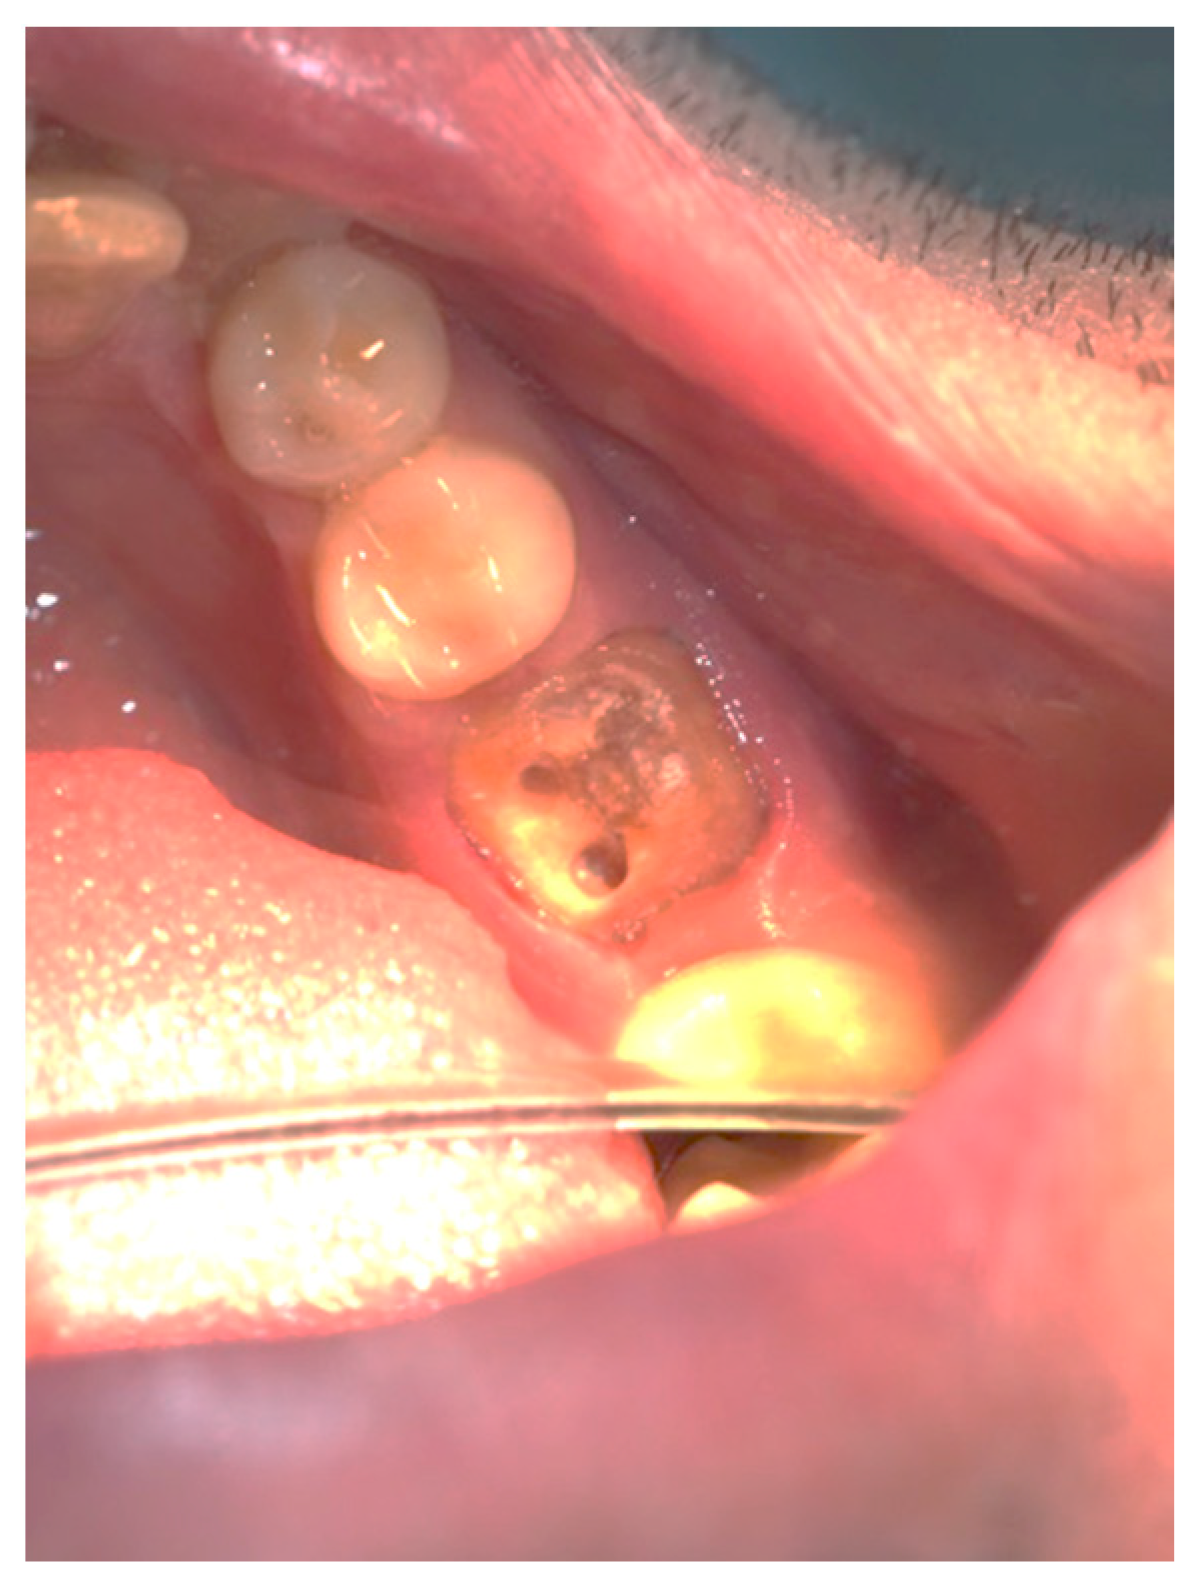

Figure 3, Figure 4, Figure 5, Figure 6, Figure 7 and Figure 8 display the follow-up of the healing process after a resective procedure for lengthening a short clinical crown with a laser.

Figure 4.

Healing at the 24th hour: the wound was covered with fibrinous plaque and an erythematous halo.